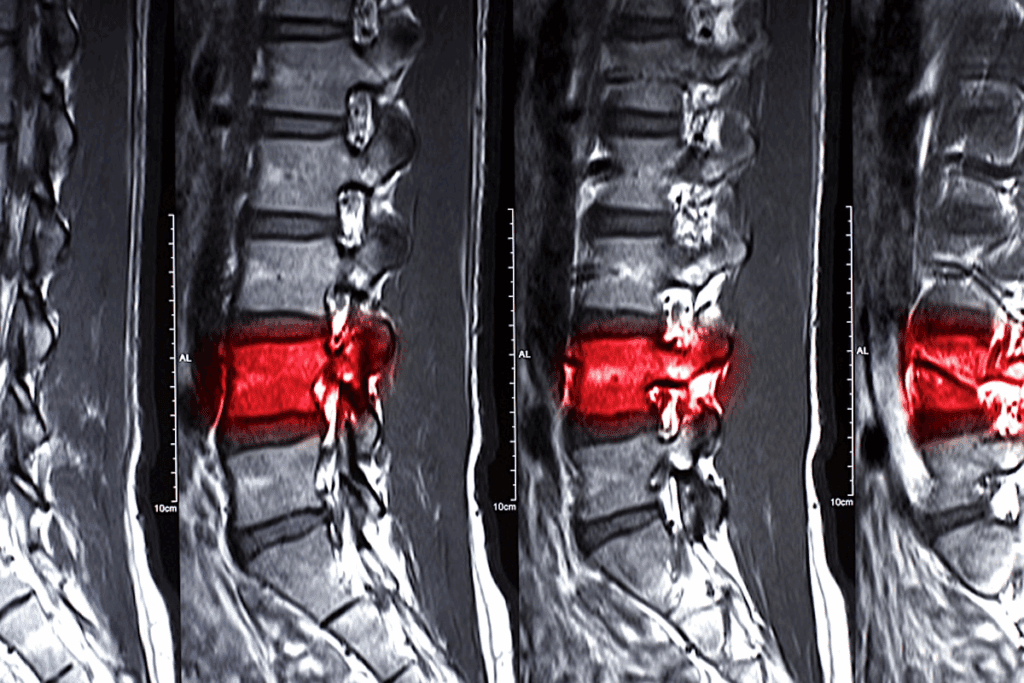

Diagnosing L5 S1 conditions involves physical exams, patient history, and imaging. MRI scans are very helpful. They show detailed images of soft tissues like discs and nerves.

Healthcare providers check muscle strength and pain during physical exams. This helps find the problem’s source. Knowing this is key for creating a good treatment plan, whether it’s l5 s1 disk protrusion treatment or other methods.

Doctors use physical exams, medical history, and MRI scans to diagnose. These methods show how much the disc bulges and its effect on nerves.